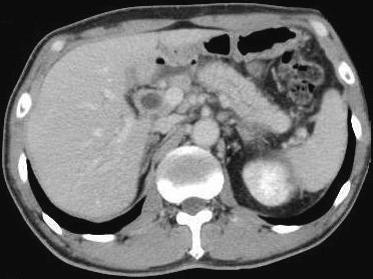

76歳の男性。黄疸を主訴に来院した。3日前に家族に皮膚の黄染を指摘されていた。3年前に唾液腺腫瘤を摘出した。飲酒は機会飲酒。意識は清明。身長168cm、体重57kg。体温36.4℃。呼吸数16/分。脈拍72/分、整。血圧126/82mmHg、眼球結膜に黄染を認める。心音と呼吸音とに異常を認めない。肝・牌を触知しない。尿所見:蛋白(-)、糖1+。血液所見:赤血球465万、Hb14.1g/dL、Ht45%、白血球8,100、血小板16万。血液生化学所見:血糖201mg/dL、HbA1c 6.7%(基準4.3〜5,8)、総蛋白9.6g/dL、アルブミン4.6g/dL、尿素室素19mg/dL、クレアチニン0.5mg/dL、総ピリルビン6.8mg/dL、AST86lU/L、ALT78IU/L、LD540IU/L(基準176〜353)、ALP1,230IU/L(基準115〜359)、Na138mEq/L、K4.OmEq/L、Cl102mEq/L。免疫学所見:CRP O.8mg/dL、抗核抗体 陽性、IgG 3,890mg/dL(基準739〜1,649)、IgA 118mg/dL(基準107〜363)、IgM 132mg/dL(基準46〜260)、CEA 2.8ng/mL(基準5以下)、CA19-9 26U/mL(基準37以下)。腹部造影CTと内視鏡的逆行性胆管膵管造影写真

検査では、軽度の肝機能障害、抗核抗体陽性、IgG高値あたり、画像では、膵臓がやたらでかい(CT)、胆管の先細り(ERCP)、膵管の狭小化・壁不正あたりが特徴らしい。私はこの疾患をよく知らないので適当なことを言ってるかもしれない。